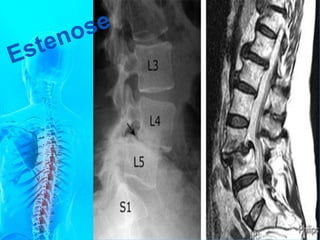

cilíndrico. Os corpos vertebrais lombares são

achatados e largos por constituírem as

vértebras que suportam as maiores pressões